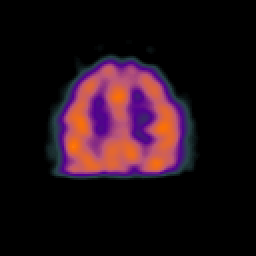

Normal aging, overlay -- Slice #39

[Home][Help][Clinical] Slice 39